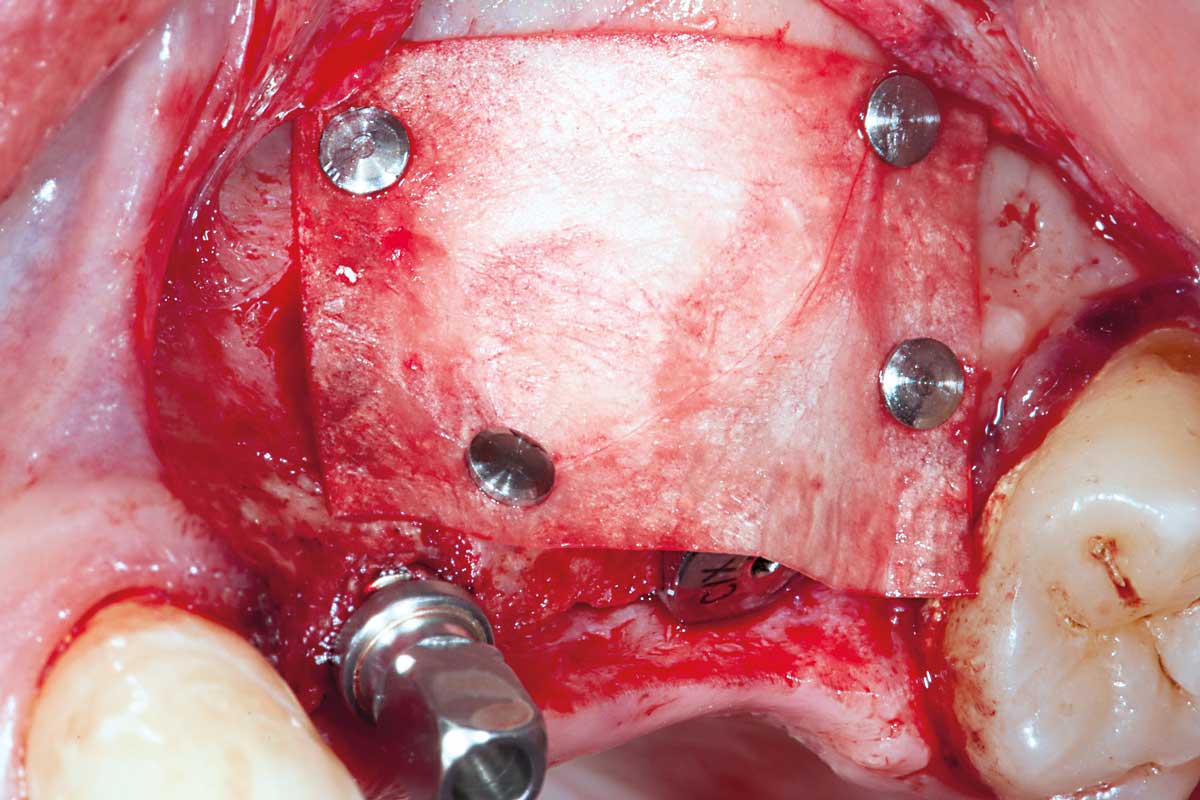

Augmentation of buccal and lingual bone lamella with maxgraft® bonering - Dr. B. Giesenhagen

X-ray scan: initial situation loss of two wall bony defect with loss of buccal and lingual lamella